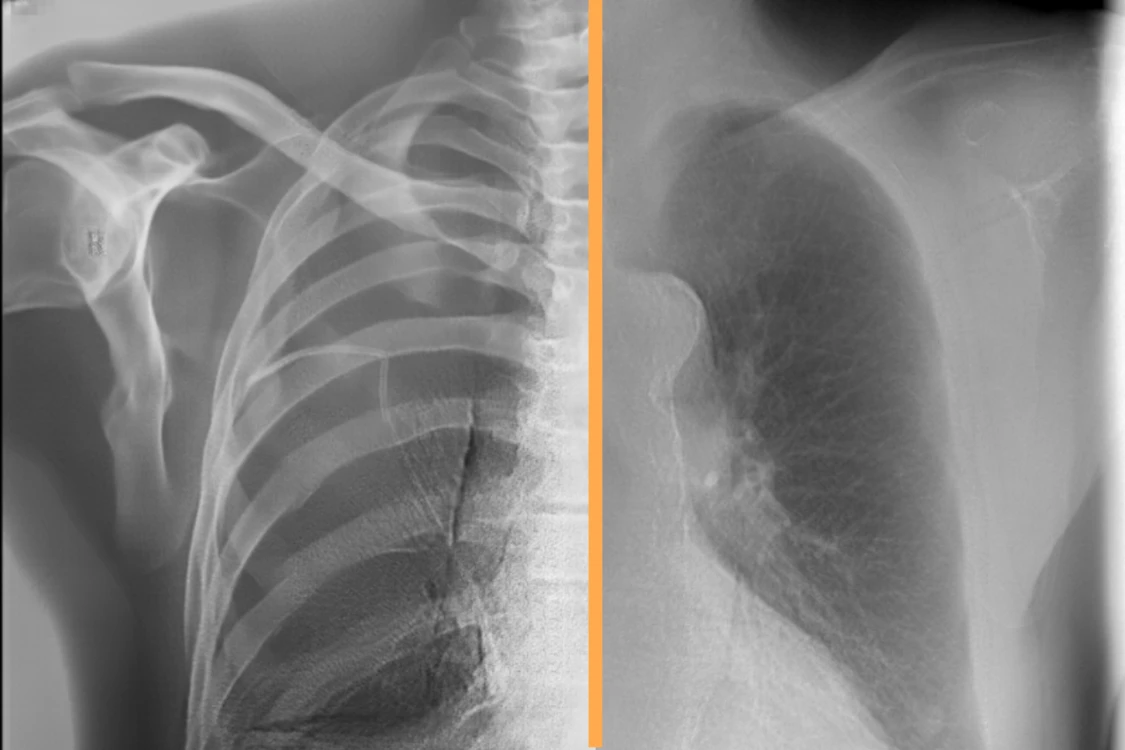

AI BONE SUPPRESSION AND SUBTRACTION

CASE PRIORITIZATIONRAYSCAPE CXR AI brings computational clarity to everyday imaging, continuously analyzing chest X-rays to surface clinically meaningful patterns that might otherwise remain buried in visual complexity. By combining broad abnormality detection with advanced image enhancement, the system helps transform raw imaging data into structured, actionable insight.